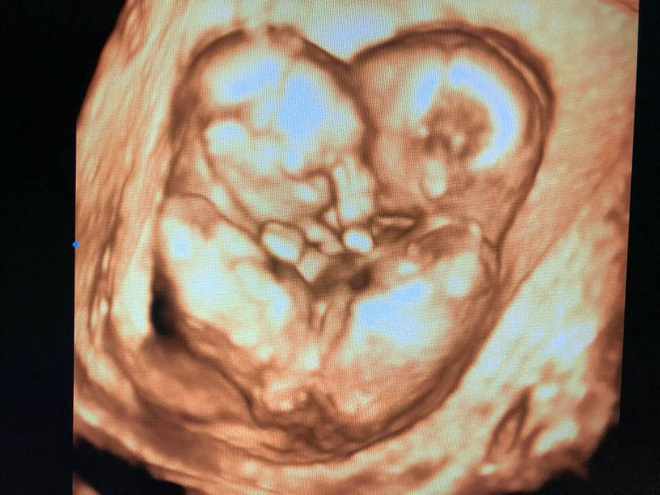

Cũng trong ngày hôm qua, trước cuộc phẫu thuật cam go và được cho là ca khó vào hàng hiếm trong lịch sử y khoa, bác sĩ Nguyễn Đình Vũ - Phó trưởng khoa Chẩn đoán hình ảnh Bệnh viện Hùng Vương đã chia sẻ lại bức ảnh siêu âm tiền sản của "Song Nhi". Bức ảnh từng được đăng tải vào ngày 28/1/2019 kèm lời nhắn: Let me tell ya something: “we’ll be born with our parents’s courage”. Tạm dịch: "Để con nói cho các bạn nghe, tụi con sẽ được sinh ra bởi lòng can trường của cha mẹ con".

Hình ảnh 1 năm trước như một lời cầu nguyện cũng như một lời động viên các bé và cha mẹ bởi sau bao khó khăn, vất vả thì thời khắc quyết định này sẽ giúp các em có cợ hội được phát triển khỏe mạnh, độc lập.

Hình ảnh đáng yêu sau đó cũng đã được fanpage "Bệnh Viện Nhi Đồng Thành Phố" đăng tải lại kèm theo dòng chia sẻ, "Hôm qua, khi các con đang chiến đấu tại phòng mổ cùng gần 100 y bác sĩ, bác Vũ và cả nước lại tiếp tục cầu nguyện cho con... Xin chân thành cảm ơn tất cả tâm nguyện của mọi người.